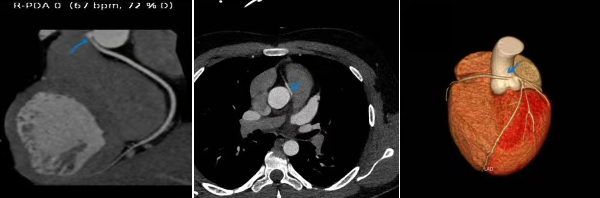

心血管内科专家结合小张的检查结果,立即为其安排冠状动脉CTA检查,谜底终于揭开:小张的右冠状动脉开口异常,本应从右冠窦开口的血管,与左冠状动脉挤在了左冠窦。正常情况下,冠状动脉像两顶小帽子覆盖心脏表面供血,而小张的右冠状动脉需绕过大弯,易被主动脉和肺动脉“夹住”。运动时心脏收缩、血管扩张,这根血管会被进一步压迫,导致心肌缺血,引发胸痛、头晕,反复缺血还会造成心肌细胞损伤,使肌钙蛋白升高。